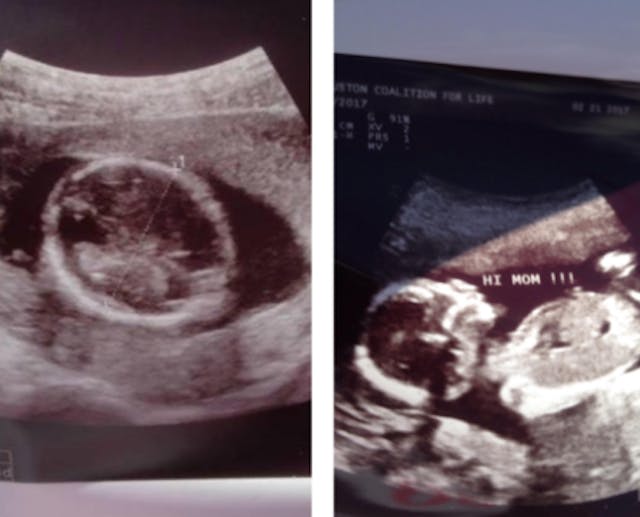

Whitehead offered Amara the chance to have another ultrasound at a mobile ultrasound unit parked outside Planned Parenthood. The unit was staffed with pro-lifers who were there to do ultrasounds on women to show them the truth about fetal development before they had abortions. Amara agreed to have another ultrasound done and Whitehead escorted her to the mobile unit.

Below is the picture that the mobile unit printed out and gave Amara. You can clearly see the head, body, arm and hand of Amara’s preborn baby.

Amara came out of the mobile unit with a big smile on her face. She showed Whitehead the picture of her baby, exclaiming: “I can’t believe it! Look! It’s a whole baby!”

Before pro-lifers showed her the truth, Amara had no idea her baby was fully developed. Planned Parenthood had led her to believe her 16 week old child was just a circular blob of tissue.

Here are the two ultrasounds, side by side (left: Planned Parenthood; right: mobile ultrasound unit):